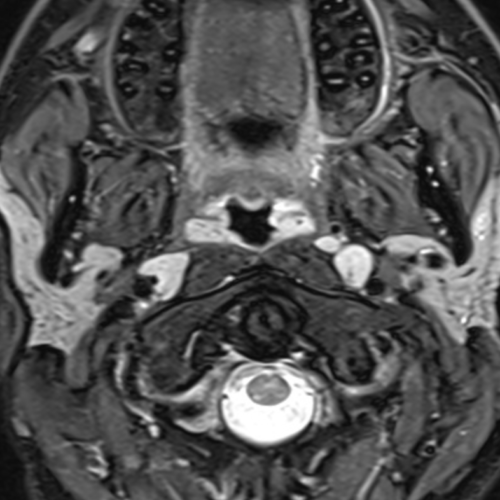

Cet examen est réalisé pour analyser les différentes structures anatomiques de la glande parotide.

La glande parotide est la plus volumineuse des trois glandes salivaires principales. Elle se situe dans la loge parotidienne, juste en dessous et en avant de l’oreille.

Cette IRM est réalisée en cas de douleurs, de masse parotidienne, de suspicion de lithiase.

Quels sont les résultats possibles d’une IRM de la parotide ?

Cette examen permets de diagnostiquer:

- Les tumeurs : Dans 80 % des cas, une masse de la parotide est bénigne, mais une exploration est toujours nécessaire.

- L’Adénome Pléomorphe : C’est la tumeur la plus fréquente.

- Caractéristique : Croissance lente, indolore, fermement élastique.

- La Tumeur de Warthin (Cystadénolymphome)

- Les Tumeurs Malignes (Cancers) : Plus rares (20 %).

- Les Pathologies Infectieuses et Inflammatoires

- Les Oreillons (Parotidite virale)

- Les Parotidites Bactériennes

- Le Syndrome de Sjögren : * Maladie auto-immune qui « assèche » les glandes salivaires et lacrymales. Les parotides peuvent être chroniquement gonflées.

- La Pathologie Lithiasique (Les « Calculs »)

- Sialose : Gonflement non douloureux lié à des troubles métaboliques (diabète, alcoolisme, troubles du comportement alimentaire).

- Kystes HIV : Chez certains patients séropositifs, des kystes multiples peuvent apparaître dans les parotides.